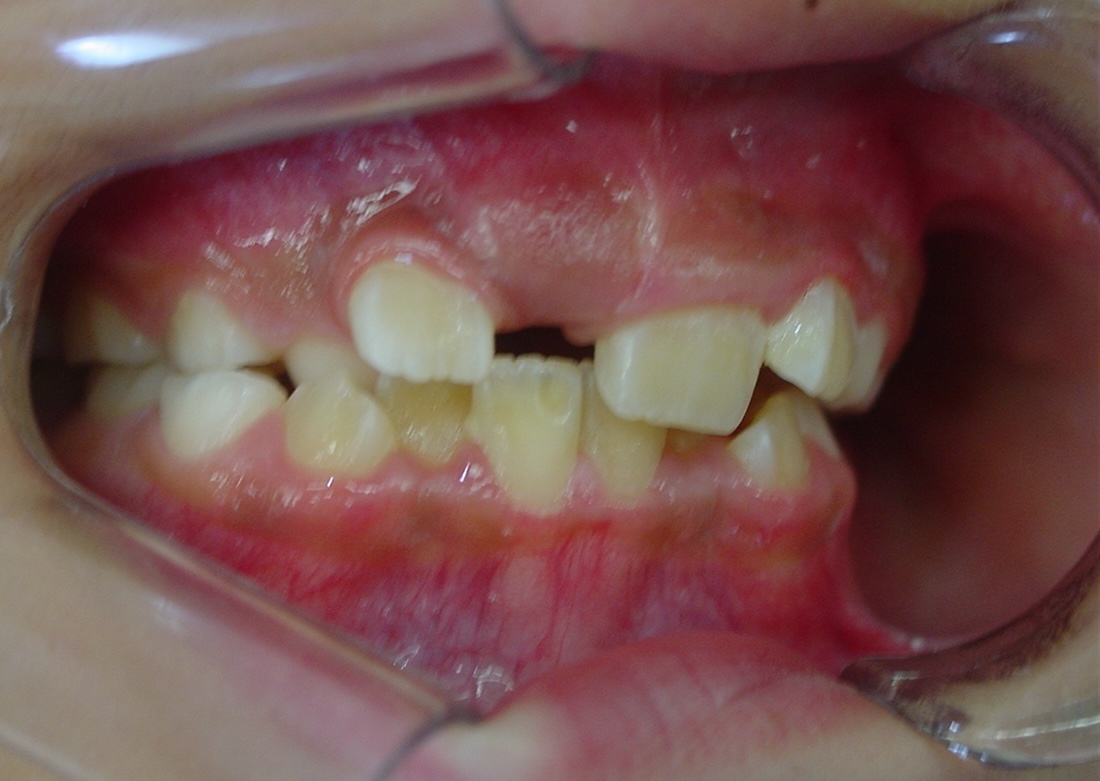

矯正前

| 症状 | 左上2番3番逆転症例 |